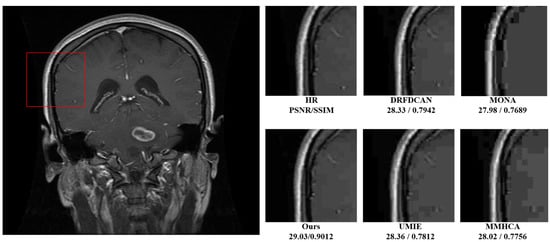

| MONA [19] | 1045 | 28.64 | 27.98/0.7689 | 27.78/0.7901 |

| MMHCA [29] | 1342 | 55.78 | 28.02/0.7756 | 27.86/0.7922 |

| UMIE [30] | 1605 | 68.32 | 28.36/0.7812 | 28.01/0.8027 |

| DRFDCAN [31] | 953 | 26.91 | 28.33/0.7942 | 29.22/0.8115 |

| Ours | 468 | 13.23 | 28.46/0.8256 | 29.48/0.8513 |